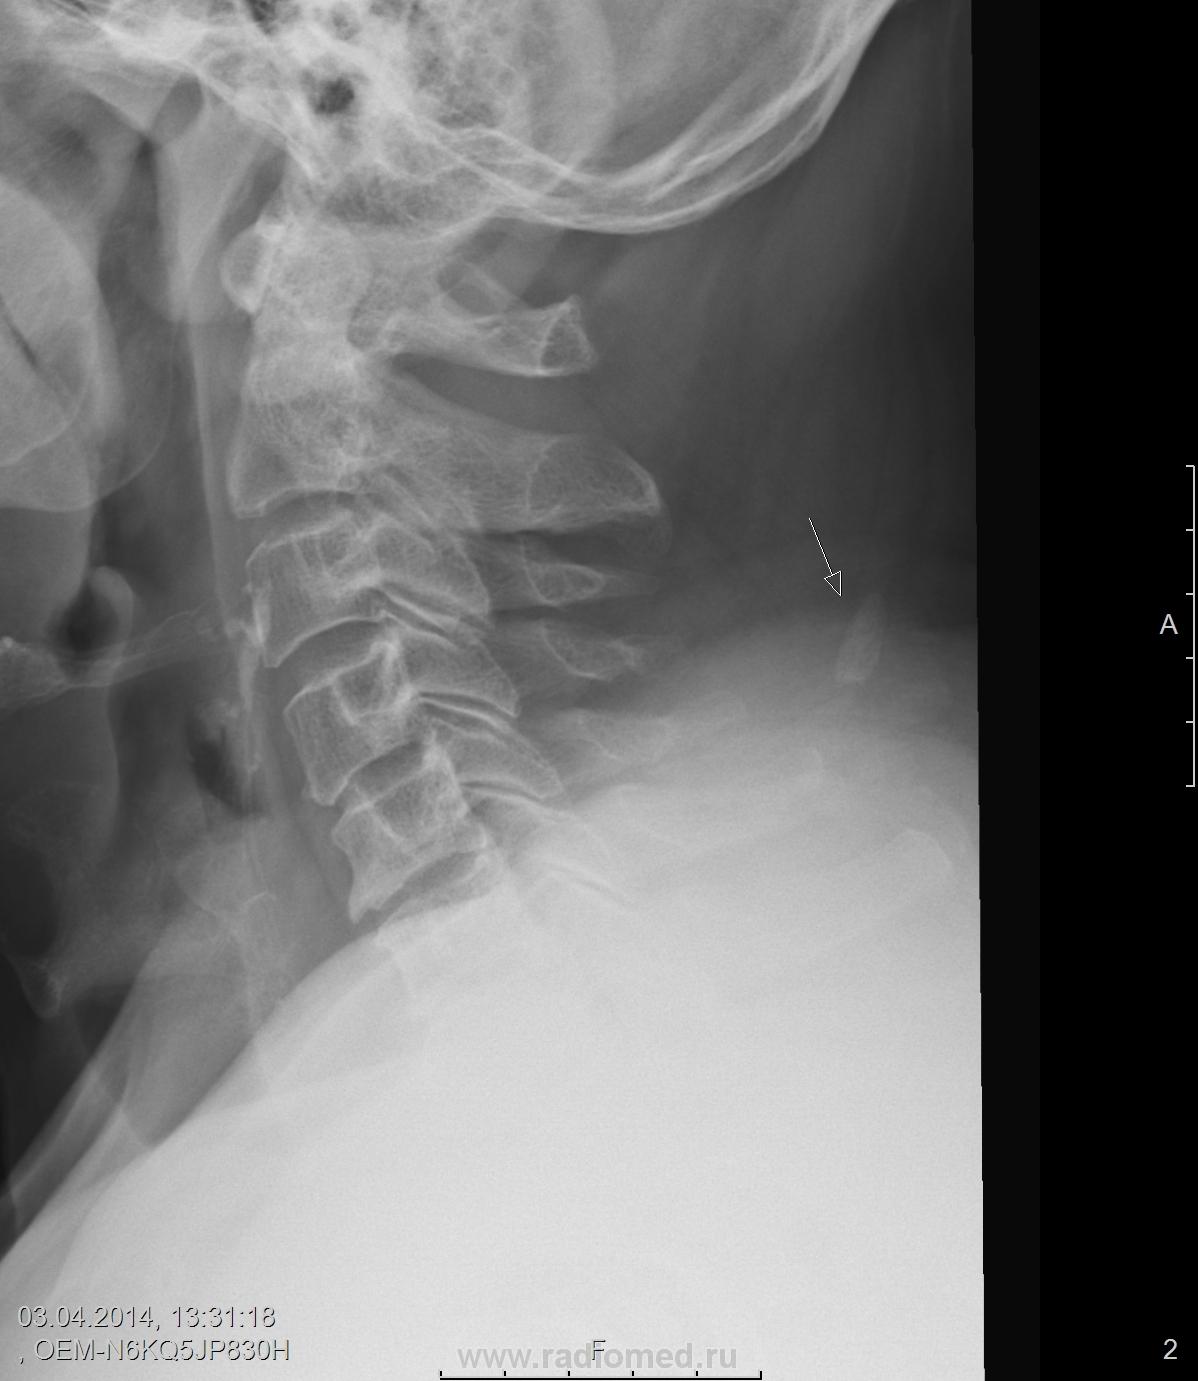

Пол пациента: Мужской пол Тип патологии: Метаболическое заболевание Область исследования: Скелетно-мышечная система Методы исследования: Rg Участок обызвествления на уровне остистого отростка С 5. https://radiomed.ru/sites/default/files/styles/case_slider_image/public/user/19785/m_c_spine_20140407_121853.jpg?itok=6bE3PY7k ID:36868 Mon, 07/04/2014 - 12:25 #1 Катенёв Валенти... Offline Last seen: 7 years 4 months ago Joined: 22.03.2008 - 22:15 Posts: 54876 Кость выйной связки. Mon, 07/04/2014 - 16:17 #2 Dr. X-ray Offline Last seen: 9 years 10 months ago Joined: 19.07.2013 - 21:06 Posts: 505 Катенёв Валентин Львович wrote: Кость выйной связки. +1 Mon, 07/04/2014 - 17:34 #3 Nela Offline Last seen: 6 years 4 months ago Joined: 12.05.2009 - 20:43 Posts: 1847 http://www.radiomed.ru/cases/sheinyi-otdel-pozvonochnika-sluchainaya-nakhodka#top Mon, 07/04/2014 - 17:38 #4 выпускник Offline Last seen: 5 years 4 months ago Joined: 15.08.2012 - 23:11 Posts: 50 похожий случай. Mon, 07/04/2014 - 19:27 #5 гана Offline Last seen: 4 years 4 months ago Joined: 12.01.2011 - 09:43 Posts: 84 +1 Mon, 07/04/2014 - 21:15 #6 И.Бондаренко Offline Last seen: 21 hours 16 min ago Joined: 13.09.2011 - 22:55 Posts: 9210 +3

Кость выйной связки.